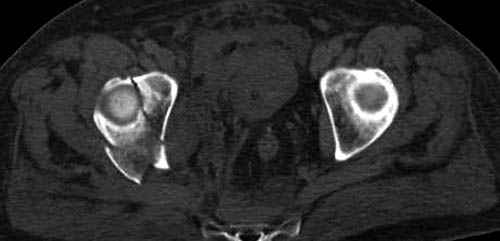

По возможности вышлите снимки, сканы таза до

реконструкции, интраоперационные.

По снимку создается впечатление о высоком поперечном переломе, задней колонны, стенки; почему не пользовались *magic screw*?

Кава фильтр при переломах таза - это протокол или только для пациентов с политравмой?

Профилактику DVT и установку кава фильтер применям

почти у всех со множественными травмами, особенно тем, кто потенциально должны находится длительно без активного движения, тем более тем, кто страдает избытком веса.

В нашем протоколе в день операции делаем допплеровскую проверку сосудов, и в координации с сосудистыми хирургами установку фильтра до начала нашей операции, современные фильтры временные, можно удалить через несколько месяцев.

Снимки здесь....